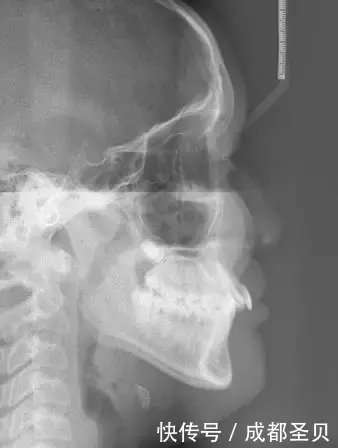

牙齿矫正是通过正畸或外科手术等方法治疗错颌畸形。牙齿矫正的基本流程主要有初诊检查,咨询治疗概况、常规